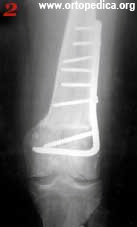

1. Рентгенограмма больного Л. до операции остеоартроз коленного сустава с вальгусной деформацией сустава